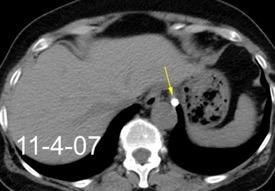

By-pass coronario 21-10-03

Síndrome de afectación postcardiaca (postcardiac injury)

Post infarto 1-7 % (Dressler)

Trauma cerrado Implantación marcapasos

Cirugía cardiaca. 17-31% (Post.pericardiotomía)

3707 pacientes 29 Derrames (0,78%) > de 25% del hemitórax

Todas menos 2 Izdos.

Angioplastia